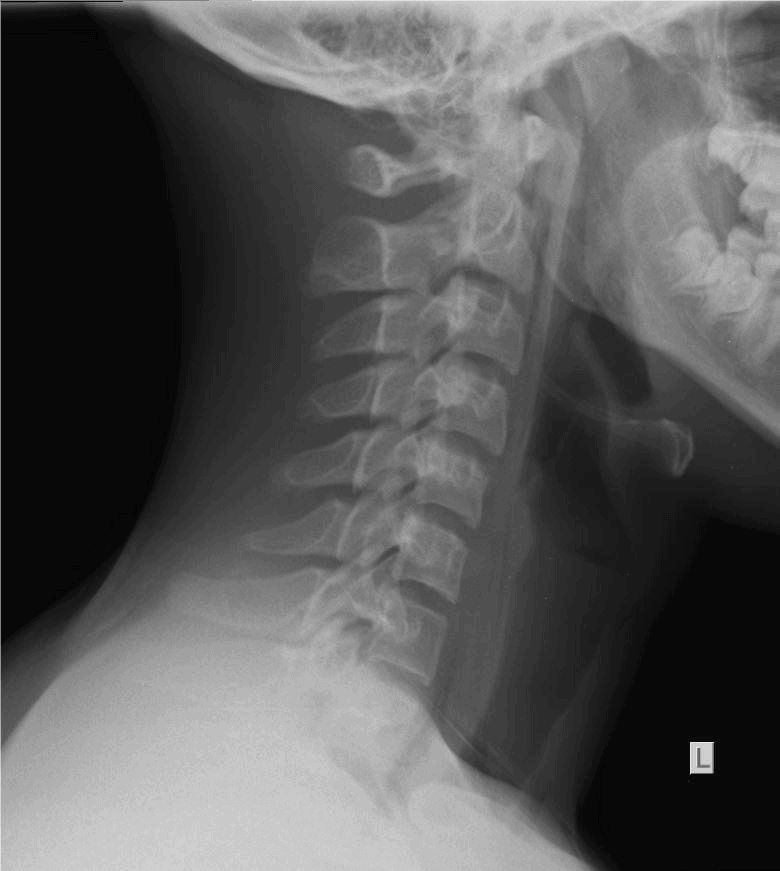

The patient is a 9-year-old girl who is brought in by her parents shortly after choking on a chicken nugget. They are concerned because even though she stopped gagging, she complains that it feels “like there’s something stuck in there.”

View the images, ordered to rule out a lodged foreign body, and consider what the diagnosis and next steps would be. Resolution of the case is described on the next page.